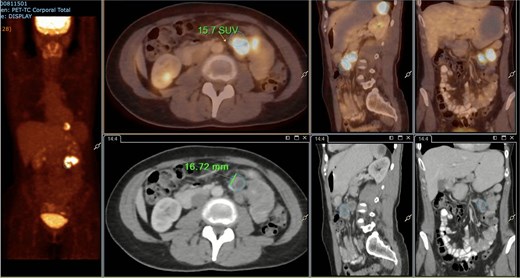

A subsequent PET/CT, performed prior to any surgical intervention, demonstrated intense radiotracer uptake in the thickened jejunal wall (SUV 17.8), in hypermetabolic mesenteric lymph nodes adjacent to the lesion (SUV 15.7), and in a 26.5-mm hypermetabolic nodule in the upper pole of the spleen (SUV 16.4) (Figs 2–4). Given these findings, lymphoma was included in the preoperative differential diagnosis.

PET/CT showing a hypermetabolic peritumoral lymph node (SUVmax 15.7).